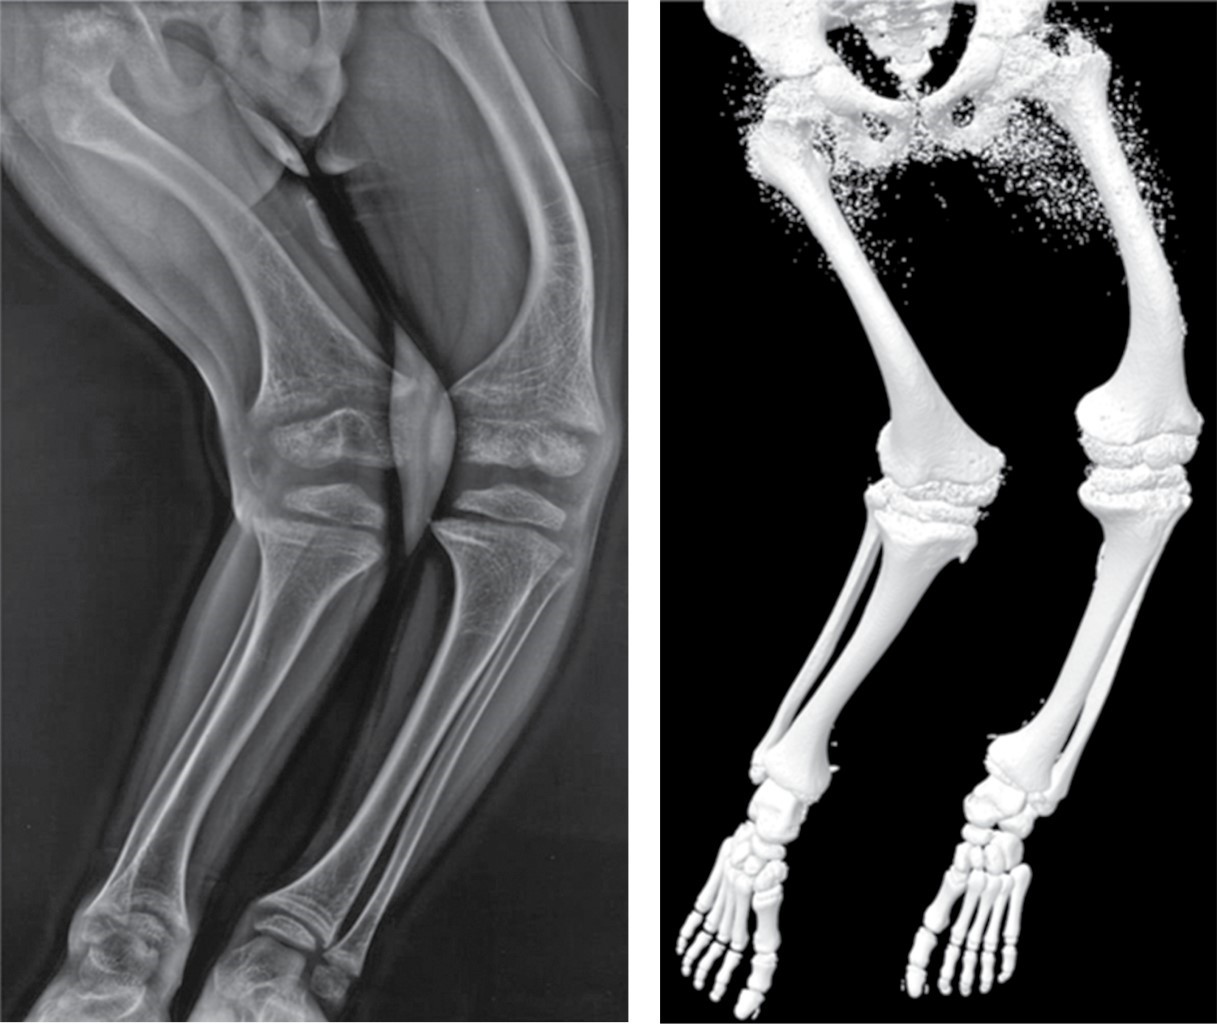

• 1. Planificación preoperatoria: la planificación preoperatoria es un paso esencial en el proceso quirúrgico. La impresión 3D permite lograr un planeamiento preoperatorio con un grado de precisión que no es posible con instrumentos convencionales.11 Así en el caso de una fractura podremos planificar la reducción de ésta y trasladar las habilidades a la práctica quirúrgica (Figura 2).

• Se ha demostrado la capacidad de la impresión 3D para representar distintos segmentos del esqueleto. La comparación de imágenes de tomografía computarizada (TC) de vértebras cervicales, torácicas y lumbares contra sus respectivos modelos impresos demostró una fuerte correlación anatómica.12